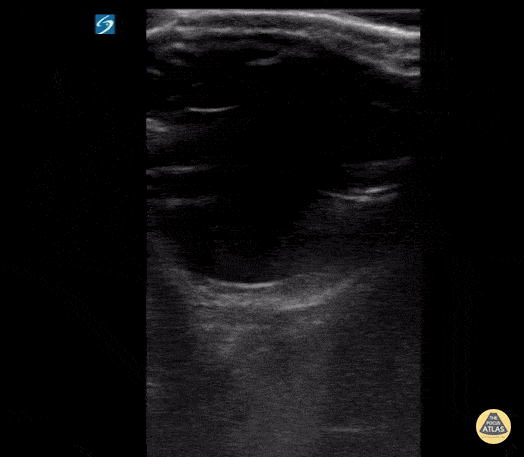

Orbital - Retinal Edema (2/2 - Clip)

17 y/o female with sudden onset bilateral blurry vision after prolonged indoor cat exposure. Fundoscopy showed retinal pigment epithelium loss consistent with bilateral neuroretinitis from cat scratch disease (Bartonella henselae). The hyperechoic retina, normally flush with the posterior aspect of the globe, is seen separated by a hypoechoic band of edema. Retinal edema from cat scratch disease is rare (Gen Opth 19th ed. 2017:378-422), but can be diagnosed by POCUS. Contributed by: John Hipskind, MD, Ultrasound Director, Kaweah Health EM Residency